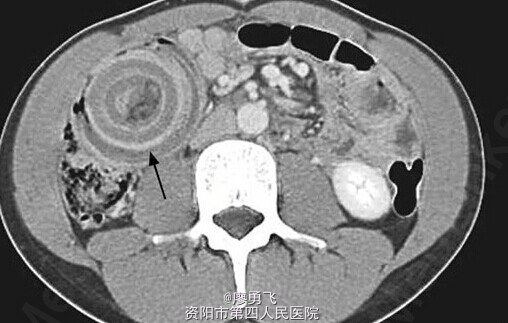

中年男性,突发腹痛6+小时入院,否认既往史,查体全服压痛,右下腹明显反跳痛;辅助检查:全腹部CT可见右下腹同心圆征象,提示肠套叠(忘了采图,附图为之前收集的,不过该病例同样典型),肾周、盆腔大量腹腔积液,不排除肠坏死可能,急诊剖腹探查,腹腔大量淡血性液体,末段回肠套入盲肠,末段回肠、回盲部、升结肠肠管呈紫红色,行右半结肠切除术,术后剖视肠管发现回盲部溃疡型新生物,术后病理提示低分化腺癌。术后病人恢复可,目前已于肿瘤科开始后续治疗。